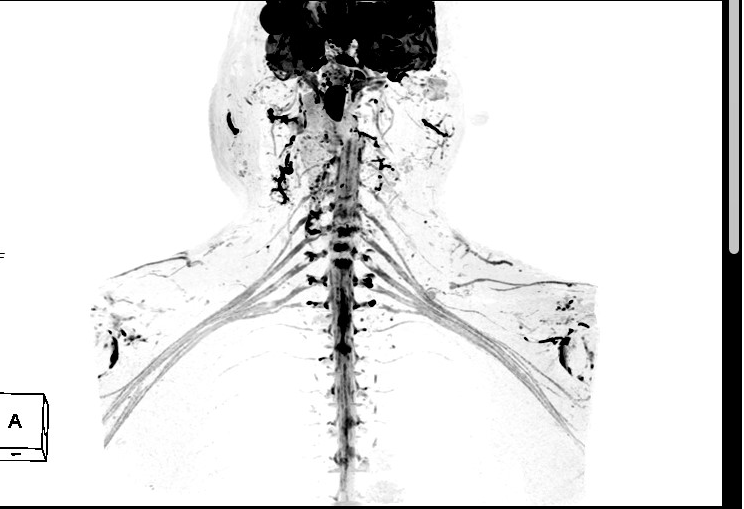

八、神经臂丛成像:此项检查技术在临床中主要应用于外伤患者有无神经丛的损伤。

联影磁共振怎么样平原县第一人民医院联影uMR780 光梭3.0T磁共振正式投入使用,开启医学影像新时代!_https://www.jmylbn.com_新闻资讯_第24张

联影磁共振怎么样平原县第一人民医院联影uMR780 光梭3.0T磁共振正式投入使用,开启医学影像新时代!_https://www.jmylbn.com_新闻资讯_第25张